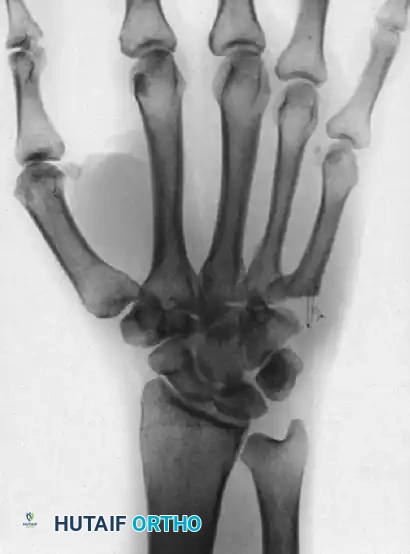

FIGURE 67-30 E and F: In this case, longitudinal traction was adequate to reduce the joints, and a well-molded splint was satisfactory to maintain the reductions.

Many acute CMC dislocations can be reduced closed. Reduction is achieved via longitudinal traction combined with direct volar pressure over the dorsally displaced metacarpal bases.

However, due to the deforming pull of the Extensor Carpi Ulnaris (ECU) tendon, these injuries are notoriously unstable. If the reduction is tenuous, percutaneous pinning is required.